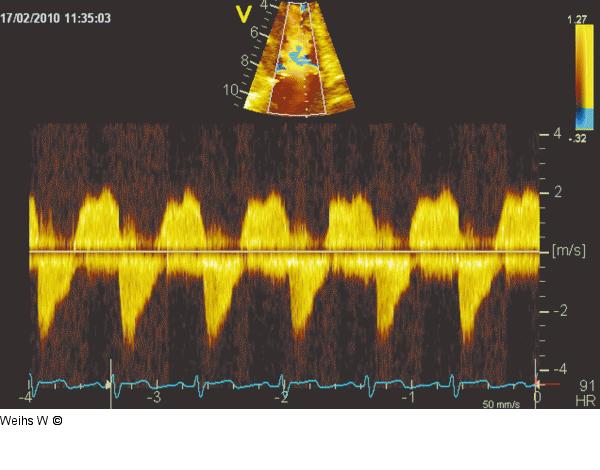

Abbildung 7: Trikuspidalklappe CW-Doppler über der Trikuspidalklappe: Als Hinweis auf die hochgradige Trikuspidalinsuffizienz zeigen sich eine trianguläre Hüllkurve mit einem frühen Peak, ein dichtes Signal sowie eine niedrige Geschwindigkeit (Druckausgleich zwischen rechtem Ventrikel und Vorhof). Der diastolische Fluss lässt eine zumindest geringfügige Stenosierung der Klappe vermuten. |